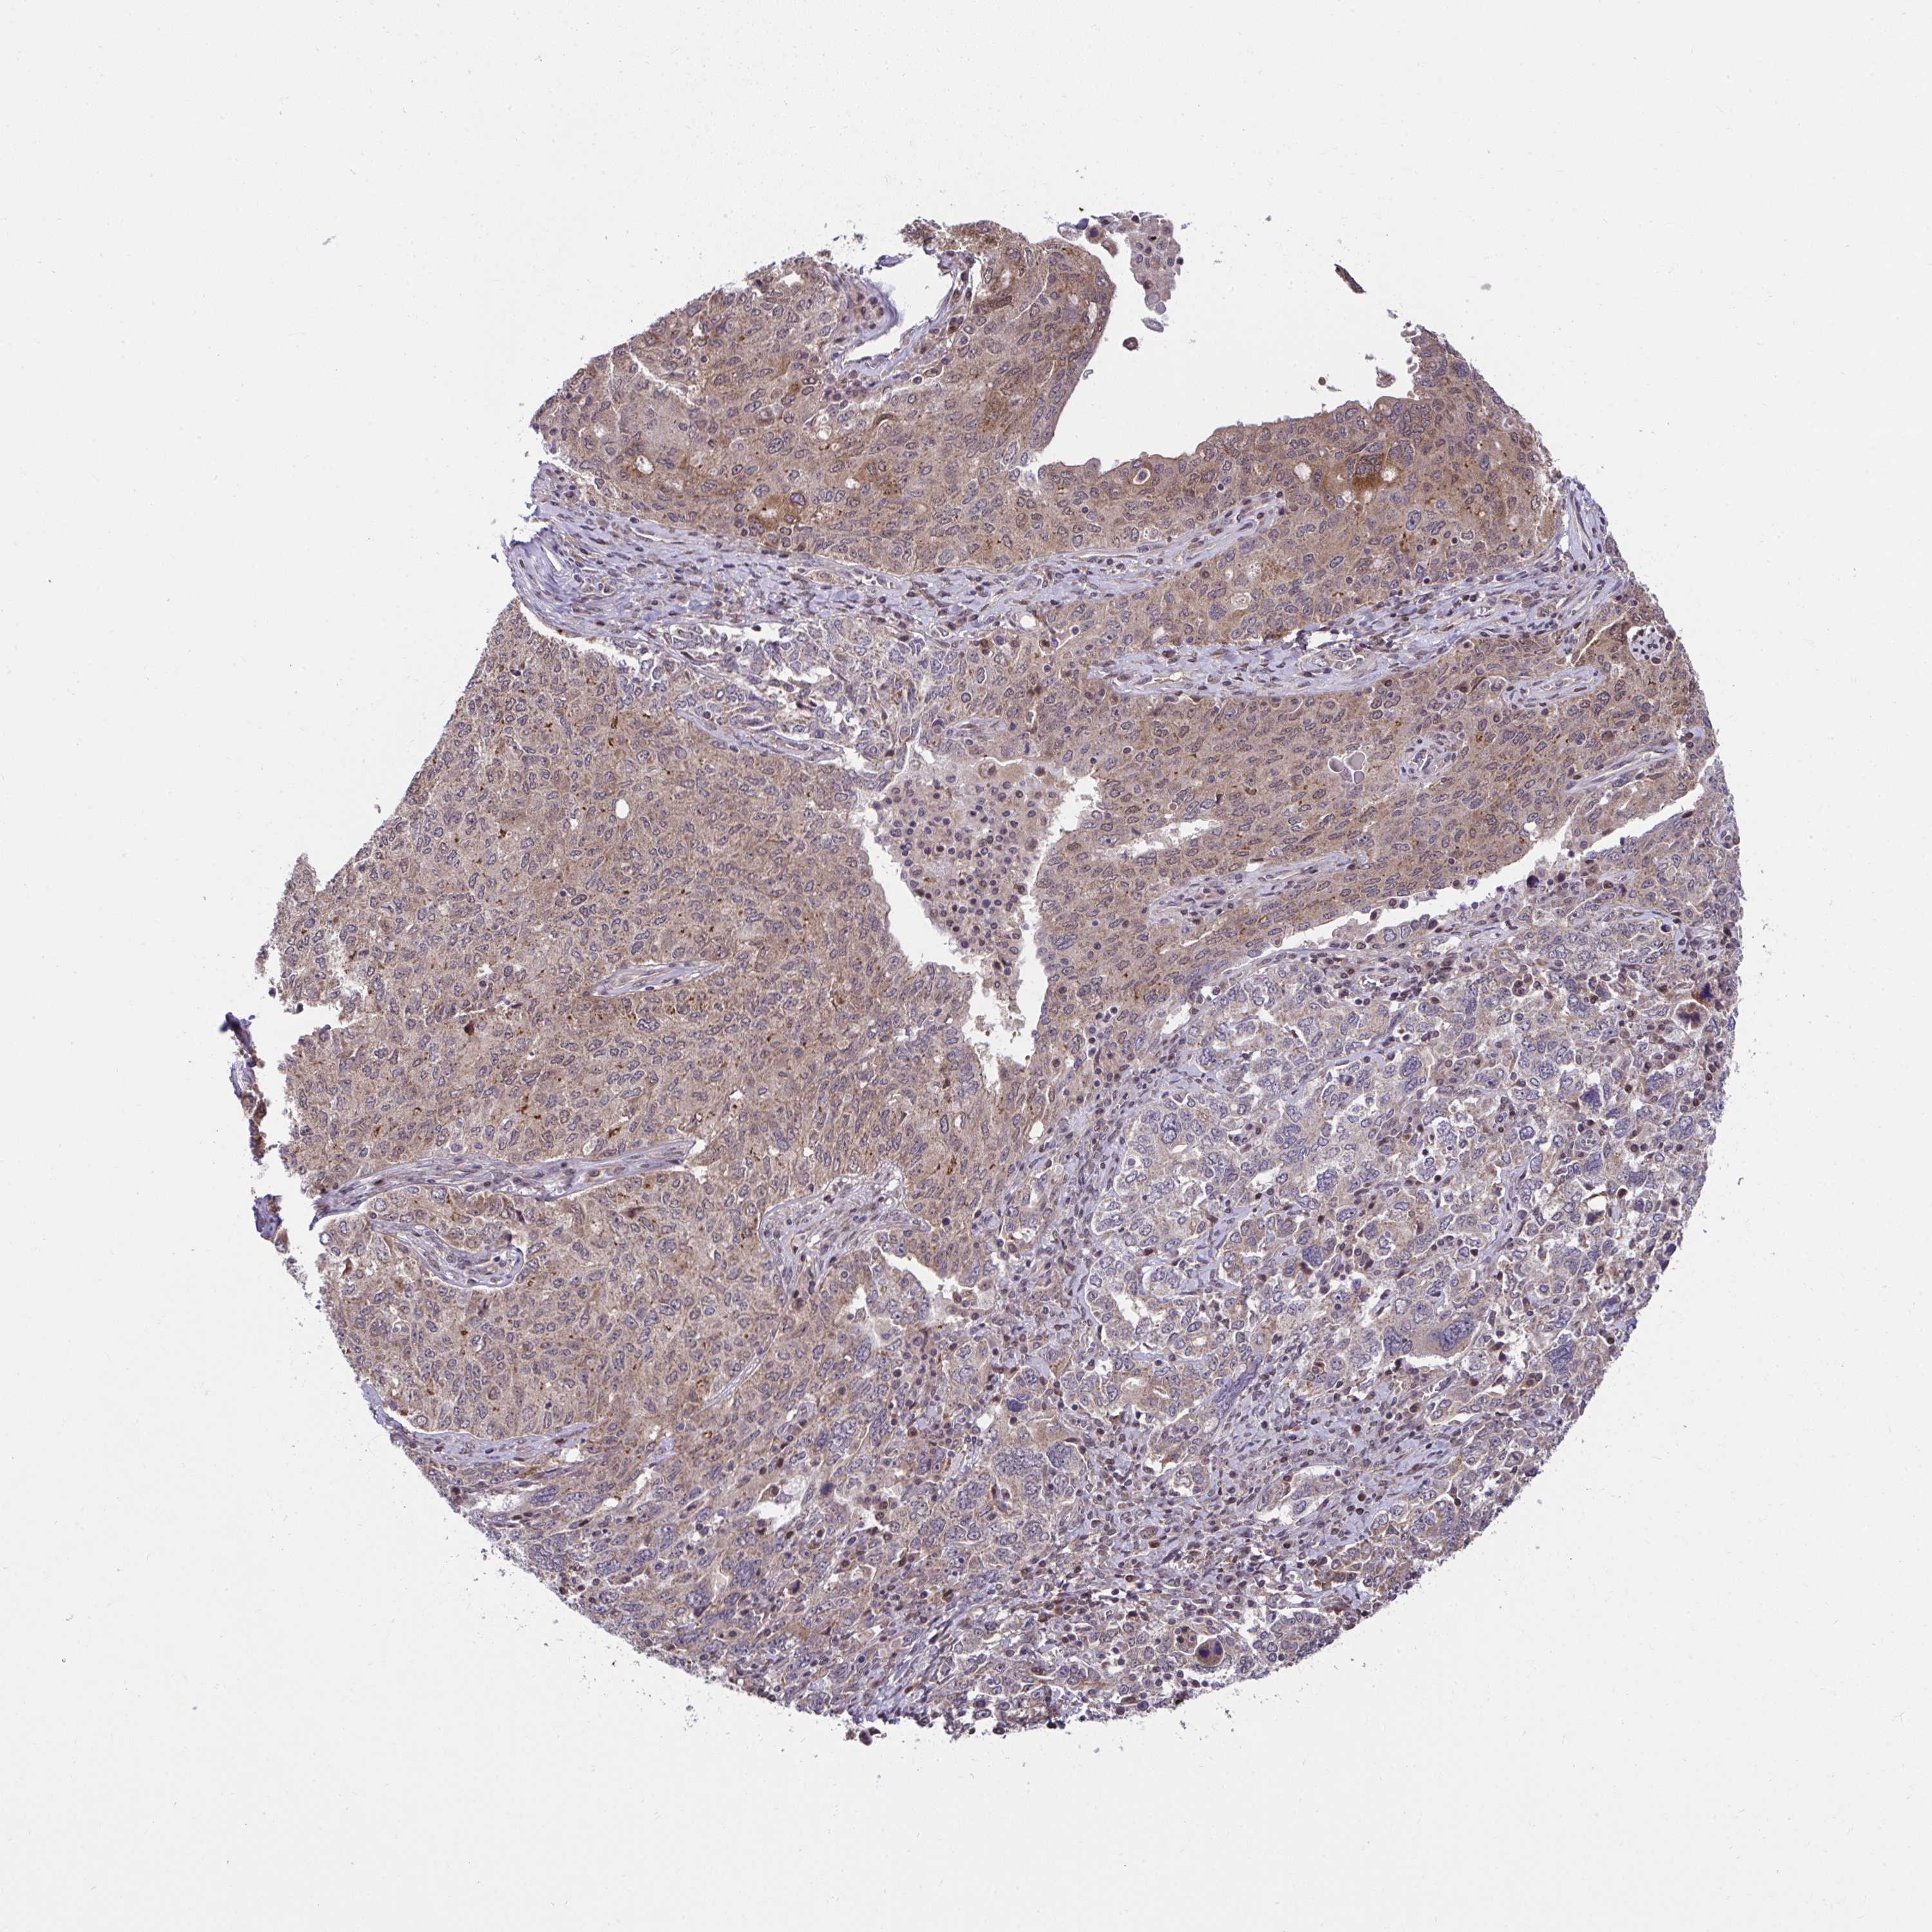

OVARIAN CANCER - Protein expressioni

A mouse-over function shows sample information and annotation data. Click on an image to view it in a full screen mode. Samples can be filtered based on level of antibody staining by selecting one or several of the following categories: high, medium, low and not detected. The assay and annotation is described here.

Note that samples used for immunohistochemistry by the Human Protein Atlas do not correspond to samples in the TCGA dataset.

Antibody stainingi

Antibody staining in the annotated cell types in the current human tissue is reported as not detected, low, medium, or high, based on conventional immunohistochemistry profiling in selected tissues. This score is based on the combination of the staining intensity and fraction of stained cells.

Each image is clickable and will lead to virtual microscopy that enables deeper exploration of all samples and also displays staining intensity scores, fraction scores and subcellular localization as well as patient and tissue information for each sample.

Antibody HPA056686

Staining

High

Medium

Low

Not detected

Intensity

Strong

Moderate

Weak

Negative

Quantity

>75%

75%-25%

<25%

None

Location

Nuclear

Cytoplasmic/membranous

Cytoplasmic/membranous,nuclear

Cystadenocarcinoma, serous, NOS

Carcinoma, endometroid

Cystadenocarcinoma, mucinous, NOS

Carcinoma, NOS